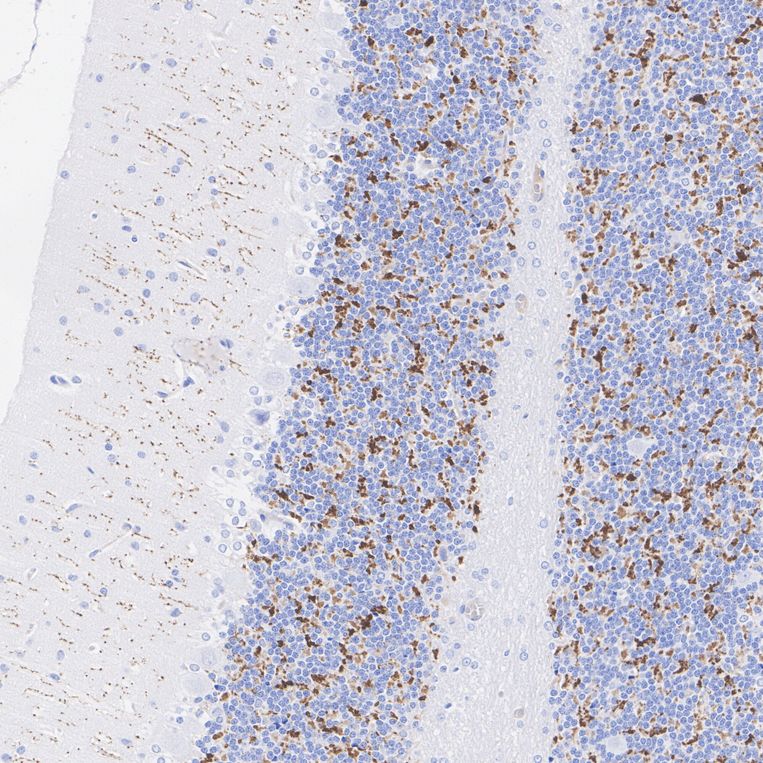

Immunohistochemical analysis of paraffin-embedded rat cerebellum tissue with Mouse anti-VGLUT2 antibody (HA610285) at 1/2,000 dilution.

The section was pre-treated using heat mediated antigen retrieval with Tris-EDTA buffer (pH 9.0) for 20 minutes. The tissues were blocked in 1% BSA for 20 minutes at room temperature, washed with ddH2O and PBS, and then probed with the primary antibody (HA610285) at 1/2,000 dilution for 1 hour at room temperature. The detection was performed using an HRP conjugated compact polymer system. DAB was used as the chromogen. Tissues were counterstained with hematoxylin and mounted with DPX.